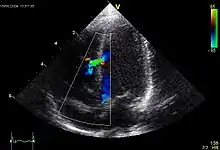

للحصول على تصوير للقلب تُستغل خاصية الأمواج فوق الصوتية في اختراق المادة والانكسار والانعكاس عند اختراق الأوساط الفيزيائية المختلفة، يحدث ذلك عند حدود هذه الأوساط. ومثال ذلك عند انتقال الصوت من الجلد إلى طبقات الدهن تحته، وكذلك عند عبور الموجات فوق الصوتية العضلة القلبية، وتظهر بالتالي حجرات القلب بشكل واضح.[1]

أثناء مرور الموجات فوق الصوتية في حجرات القلب، فإن الدم يحمل هذه الموجات بعيداً، وبالتالي لا يعكس هذه الأمواج، مما يجعل الحجرات القلبية تظهر فارغة (باللون الأسود)، بينما يكون الانعكاس عن جدران القلب والصمامات أوضح، ويزداد وضوحاً في حالات تكلّس هذه الأجزاء.[2]

في طب القلب تستخدم موجات فوق صوتية بتردد يتراوح ما بين 2.0 - 3.0 ميجاهيرتز، والتي تصل لأعماق أكبر في جسم الإنسان، مما يسمح بمشاهدة كامل حجرات القلب، ويكون ذلك على حساب قدرة التمييز (بالإنجليزية: Resolution) ودقة الصورة.[3]